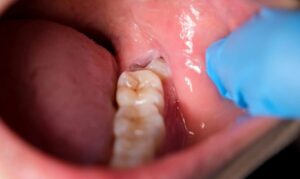

3.4 Gum Flap (Pericoronitis) Around Wisdom Teeth

A partially erupted tooth may have gum tissue covering it, which can become infected or swollen. This area easily traps food and bacteria, causing persistent pain and unpleasant odor. Gum flaps are especially common with lower wisdom teeth and often require surgical removal or other treatments.